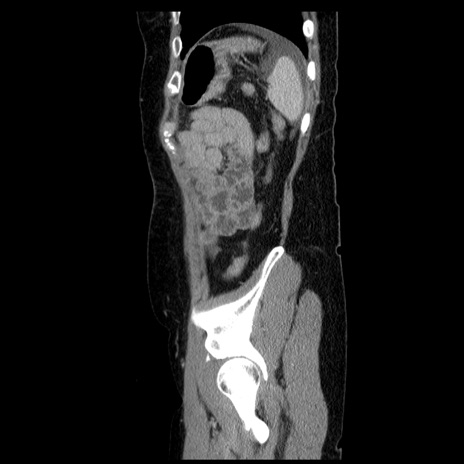

症例6(矢状断像)

【症例】50歳代女性

【主訴】下腹部痛

【既往歴】卵巣癌術後(8年前に当院で卵巣摘出)